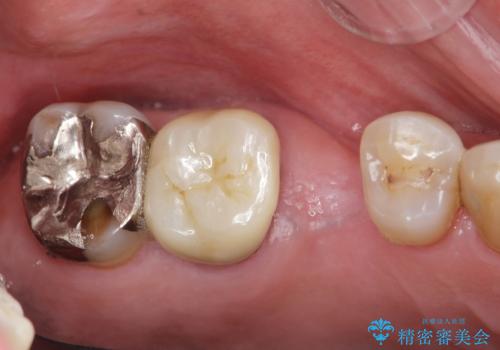

失った奥歯のインプラント治療

「失った1本の歯の機能回復を行うだけでもずいぶん咬めるようになった。」、と咬合機能の回復を実感していただくことができました。